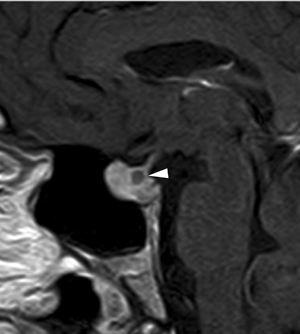

Figura 26A y B. Cortes sagitales T1w antes y después de la inyección de Gadolinio. Quiste de Rathke (puntas de flecha) de la variedad A en T1W, su señal aparece similar a la hipófisis cuando esta se refuerza con el contraste.La intensidad de señal del quiste de Rathke es variable y no ayuda a distinguir los quistes no neoplásicos de los neoplásicos62,63, pero el refuerzo de la pared tumoral es esencial en el diagnóstico de un quiste tumoral64. La presencia de nódulos intraquísticos es frecuente en quistes de Rathke, que tienen hiperseñal en T1w e hiposeñal en T2w, lo que es útil en casos en que el líquido del quiste muestra señal elevada en T1w65. Con el uso de gadolinio no se refuerzan, aunque la glándula pituitaria comprimida por el quiste puede simular una pared que se contrasta (Figuras 27A, 27B y 27C). Los quistes de la bolsa de Rathke contienen material mucoide y colesterol, son hiperintensos (70%) en T2w (Figura 6). En T1w la mitad de los quistes de Rathke presentan una señal hiperintensa heterogénea (Figura 6). En imágenes FLAIR, que es una secuencia ponderada en T2 con atenuación de la señal del líquido cefalorraquídeo, el quiste pude aparecer hiperintenso66.

Los quistes de la bolsa o hendidura de Rathke son quistes selares y supraselares congénitos, no neoplásicos, derivados de remanentes de la bolsa de Rathke. En autopsias se encuentran con una frecuencia de 13% a 22%60. Con la amplia disponibilidad de las neuroimágenes (TAC y RM), estos quistes se descubren frecuentemente como hallazgos incidentales y en general miden menos de 3 mm (Figuras 25A, 25B y 25C) y son comúnmente asintomáticos ya que su tamaño en general no produce compresión de las estructuras vecinas. Si se observa un desplazamiento anterior del infundíbulo se puede considerar el diagnóstico de un quiste de Rathke debido a su origen en la pars intermedia. Los quistes de Rathke sintomáticos son raros y comúmente se presentan como lesions intraselares; un tercio de ellos presenta ubicación supraselar61 (Figuras 26 A y 26B). Los quistes de mayor tamaño pueden presentarse con compresión del quiasma óptico, hipopituitarismo, diabetes insípida y cefalea. Pueden ser difíciles de distinguir en exámenes radiológicos de los craniofaringiomas quísticos o de los adenomas pituitarios quísticos; en estos casos la presencia de diabetes insípida sugiere que el quiste no es un adenoma pituitario.